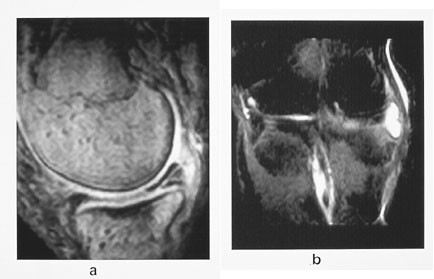

Ved akutte og gjentatte traumer ser man etter skader i menisker, korsbånd, kollateralligamenter og brusk og økt væskeansamling i trabeklene «beinkontusjon» (2, 3). Ofte finner man multiple skader. MR brukes mer og mer i utredningen av intraartikulære kondylfrakturer (4). Ved osteonekrose kan man få informasjon om hvorvidt forandringene er potensielt reversible eller irreversible. MR er blitt svært viktig hos pasienter med akutt låst kne, hvor det viser seg at de kan bli spart for akutt artroskopi (3).

Beinkontusjon foreligger når det er økt væskeansamling mellom trabeklene i forbindelse med et akutt traume og skyldes blødning og/eller ødem (4). Man oppfatter dette som mikrofrakturer. Væskeansamlingen gir økt signal på T2-vektet sekvens. STIR-sekvensen er meget sensitiv til å påvise selv små områder med væske (fig 9). Patologisk signal kan sees opptil 6–8 uker etter det aktuelle traumet. Denne væskeansamlingen forårsaker smerter som kan forklare pasientens symptomer når de intraartikulære strukturer for øvrig er intakte. Beinkontusjon kan diagnostiseres overalt i skjelettet hvor det har vært adekvat traume.

Ved kroniske knesmerter kan man med MR påvise eventulle osteonekroser med ledsagende margødem lenge før forandringene er synlige ved konvensjonell røntgenundersøkelse, og man kan som oftest også si noe om hvorvidt forandringene er potensielt reversible eller irreversible. Ved tidlig osteonekrose vil det være et subkondralt område på vektbærende del av aktuelle kondyl med nedsatt signal på T1-vektet sekvens. Gradientekkosekvenser er spesielt velegnet. Dette er ledsaget av margødem, som viser økt signal på STIR-sekvensen. Hvis det i tillegg kan påvises et subkondralt avstøtt fragment på mer enn 14 ⋅ 4 mm, er forandringen potensielt irreversibel.